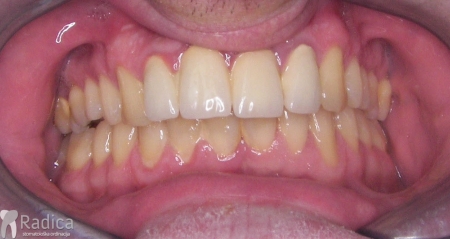

U sljedećem primjeru je fiksna ortodontska terapija rađena samo u donjoj čeljusti. Nakon toga su napravljeni novi protetski radovi u gornjoj i donjoj čeljusti – rad dr. Gorana Radice.

Na sljedećoj slici se mogu vidjeti početak i kraj ortodontske i protetske terapije. Protetske radove radio je dr. Goran Radica.